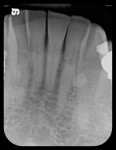

A 78-year-old male patient presented with a history of oral cancer of the right parotid gland that necessitated its removal more than 25 years ago. This resulted in severely restricting the patient’s ability to open wide on his right side (Figure 3). Consequently, it would be difficult, if not impossible, to use a rigid sensor to capture radiographs with this patient. Instead, a flexible phosphor sensor was used to capture the necessary images of the patient’s dentition with no difficulty or discomfort (Figure 4 through Figure 8).